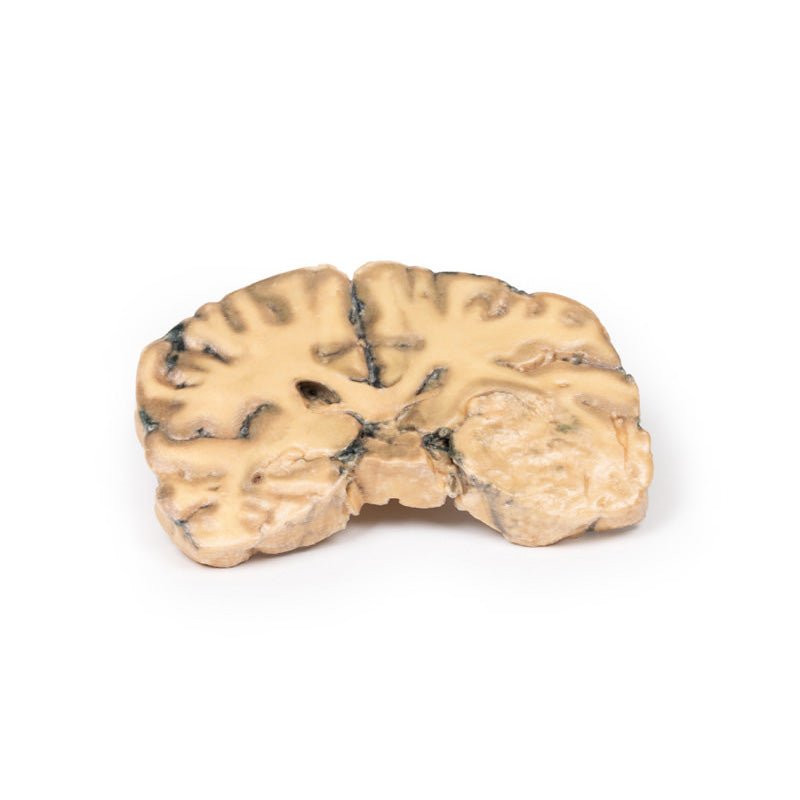

3D Printed Astrocytoma

Clinical History

A 73-year-old female was admitted with new left-sided hemiplegia. On further questioning she

revealed a 3-month history of headaches, nausea and deteriorating balance. CT brain revealed an inoperable brain

tumour. She died 1 week after being admitted.

Pathology

This brain specimen is a coronal section. In the right temporal lobe, a poorly demarcated tumour is

present. There is enlargement of the hemispheres and flattening of the gyral pattern. From the posterior aspect

of the specimen subfalcine herniation* is appreciated and the tumour appear less well differentiated with

haemorrhagic and necrotic foci. Histology of this tumour showed an astrocytoma, Grade III/IV.

*In subfalcine

(or cingulate) herniation, the most common type of brain herniation, the innermost part of the frontal lobe is

pushed under part of the falx cerebri, between the two hemispheres of the brain.